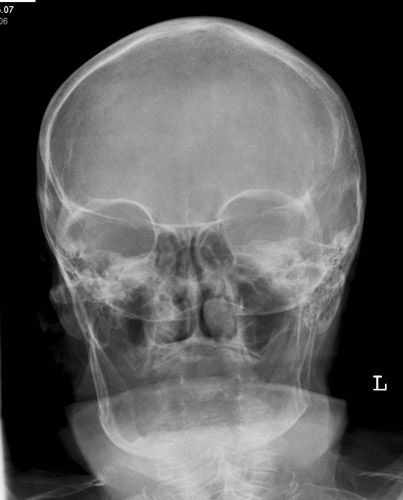

NNH p.a.

49_3.jpg

Fehler

Projektion der Felsenbeine in die diagnostisch wichtigen unteren Abschnitte der Kieferhöhle, in welchen sich bei einer frischen Sinusitis der Erguss ansammelt (auf der Aufnahme bei sitzendem Patienten!)

Abhilfe

Nasenspitze geringfügig vom Film abheben lassen, mit anderen Worten Kinn mehr vorstrecken; Kopf mehr nach hinten nehmen.